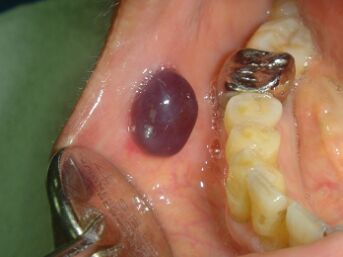

6.下列黏膜下出血的圖中,何者是瘀斑(petechiae)? (A)(B)(C)(D)

11.關於齒間牙齦病變的鑑別診斷,下列敘述何者最不可能? (A)外觀紫紅色,稍有潰瘍,碰觸時容易流血,則可能為化膿性肉芽腫(pyogenic granuloma) (B)摸起來很硬,外觀呈淡粉紅色,則可能為周邊性骨化纖維瘤(peripheral ossifying fibroma) (C)摸起來很軟,且外表呈現微黃色時,則可能為黏液囊腫(mucocele) (D)用力擠壓時,病變由暗紅色變淡色,則可能為血管性病變